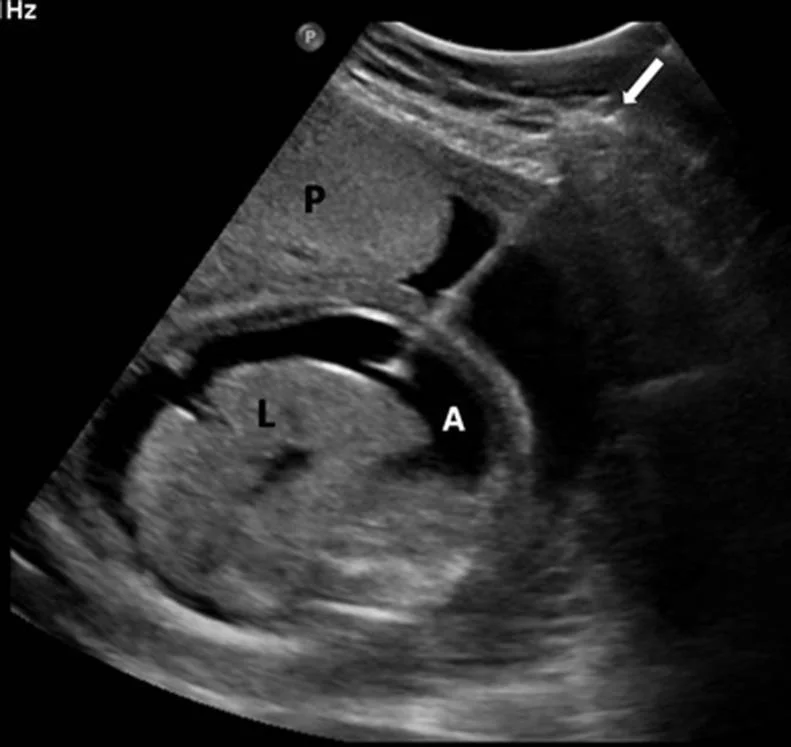

Hydrops Fetalis Ultrasound

Hydrops Fetalis

Definition and Characteristics

• Is a form of in utero heart failure.

• In the setting of Rh alloimmunization, it is characterized by the presence of:

• Fetal ascites.

• Pericardial effusion.

• Pleural effusion.

• Subcutaneous edema (best seen as scalp edema).

• Polyhydramnios.